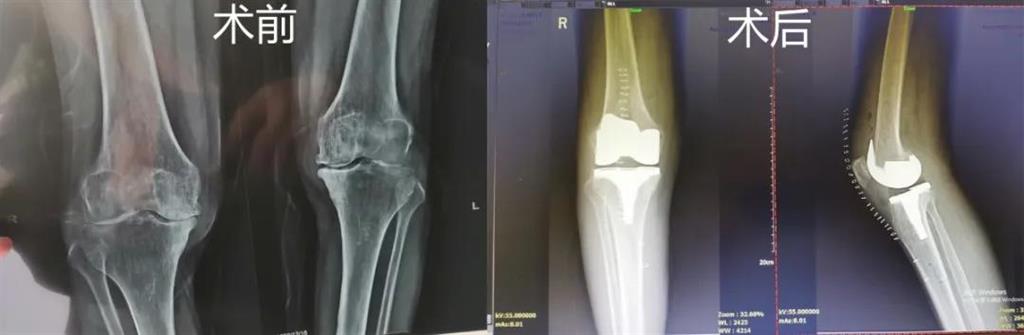

和平國(guó)際醫(yī)院副院長(zhǎng)、骨科中心主任劉丹在診斷后發(fā)現(xiàn),老人雙側(cè)膝關(guān)節(jié)患有骨性關(guān)節(jié)炎,右側(cè)膝關(guān)節(jié)較為嚴(yán)重,而且關(guān)節(jié)磨損嚴(yán)重,關(guān)節(jié)間隙基本消失。

經(jīng)過(guò)進(jìn)一步檢查后,劉丹帶領(lǐng)團(tuán)隊(duì)在計(jì)算機(jī)導(dǎo)航系統(tǒng)的輔助下,為老人實(shí)施了右側(cè)全膝關(guān)節(jié)置換手術(shù)。術(shù)中出血明顯減少,術(shù)后疼痛腫脹等反應(yīng)輕微,畸形矯正力線恢復(fù)理想,而且功能恢復(fù)快速,術(shù)后四天就可以下地行走。